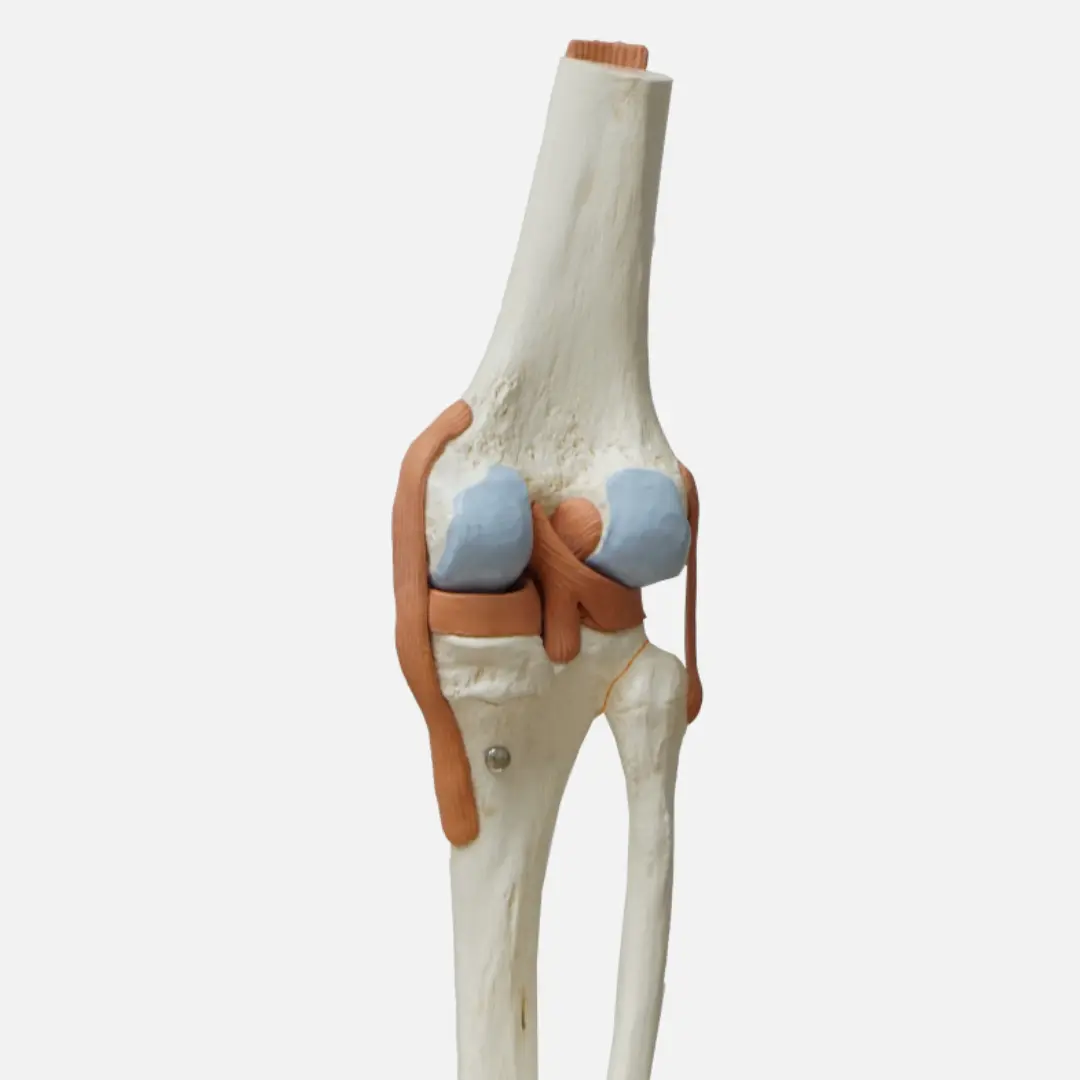

무릎 통증은 매우 흔하며, 그 원인도 매우 다양해요. 무릎 관절을 이루는 뼈, 연골, 인대, 힘줄, 근육 등 어느 부위에 문제가 생겨도 통증이 발생할 수 있습니다.

- 반월상 연골판 손상: 무릎 관절 내 충격을 흡수하는 반월상 연골판이 찢어지거나 손상되는 경우예요. 쪼그려 앉거나 무릎을 굽히고 펼 때 통증, '딸깍'거리는 소리, 무릎이 잠기는 느낌(잠김 현상) 등이 나타납니다.

- 반월상 연골판 손상:

- 원인: 무릎 충격을 흡수하는 반월상 연골판이 찢어지거나 손상되는 경우예요. 쪼그려 앉거나 무릎을 비트는 동작에서 흔히 발생합니다.

- 증상:

- 무릎을 굽히고 펼 때, 쪼그려 앉을 때 통증이 심해져요.

- 무릎에서 '딸깍'거리는 소리가 나거나 무릎이 잠기는 듯한 **'잠김 현상'**이 발생할 수 있어요.

- 무릎이 붓고 움직임이 제한될 수 있습니다.